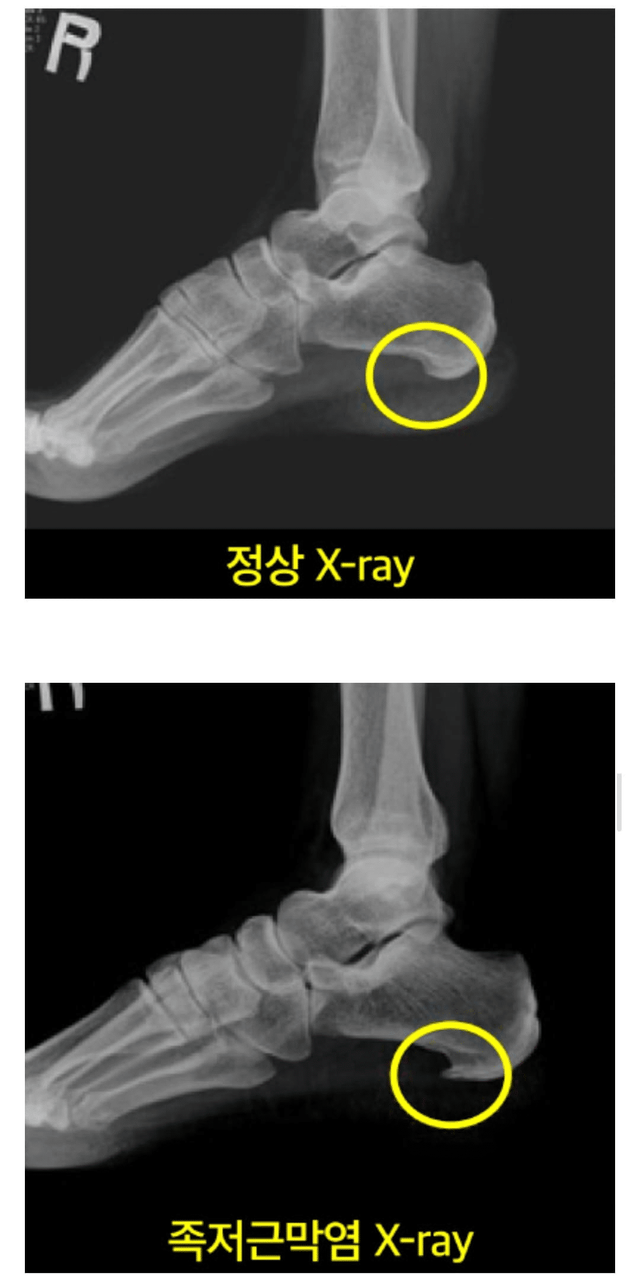

족저근막염 내버려두면 발바닥에 뿔도 생김,,